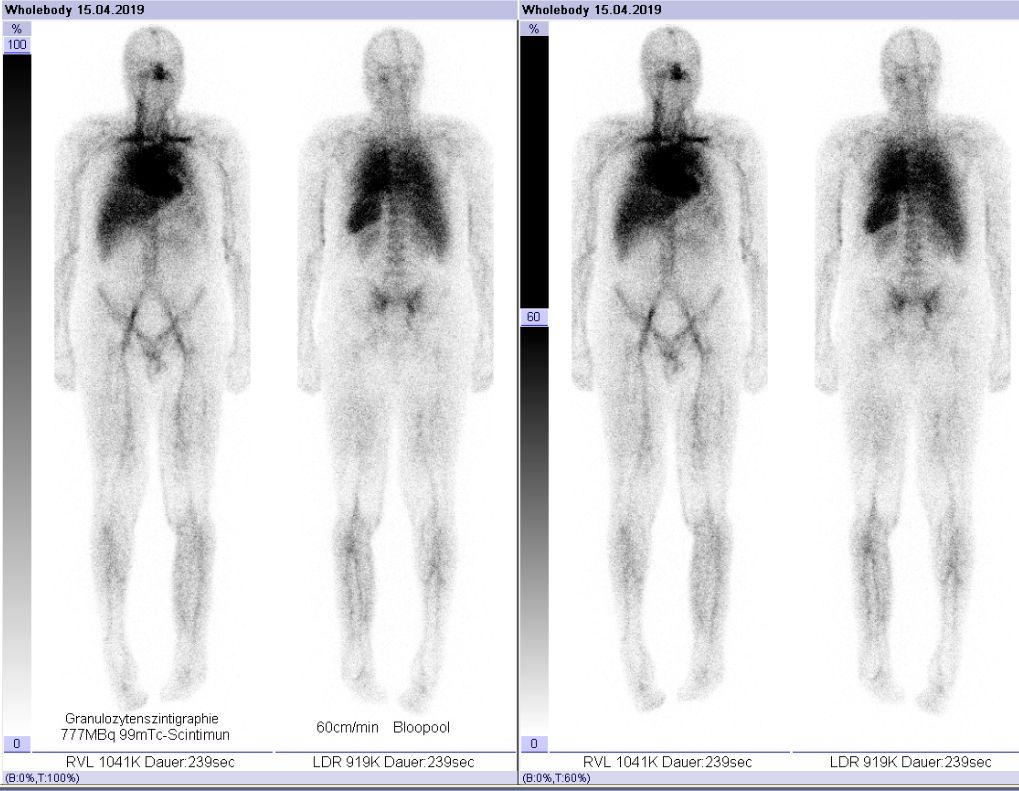

Mit einer Entzündungs-Szintigraphie können wir Entzündungen im Körper auffinden. Sie wird häufig eingesetzt, um Entzündungen im Bereich von Prothesen oder in Weichteilgewebe darzustellen. Dabei macht man sich das Wissen zunutze, dass weiße Blutkörperchen (Granulozyten) an akut entzündeten Stellen besonders konzentriert auftreten, weil sie eine wesentliche Rolle im Abwehrsystem spielen. Für eine Entzündungs-Diagnose werden mehrere Szintigrafie-Aufnahmen mit einer Gamma-Kamera angefertigt. Hierfür sind mehrere Aufnahmen an zwei aufeinanderfolgenden Tagen erforderlich.

Das Medikament wird bei Untersuchungsbeginn gespritzt und es werden sofort Bilder von der vermuteten Entzündungsregion gemacht. Für alle Aufnahmen bitten wir den Patienten möglichst ruhig zu liegen. Anschließend wird die erste Ganzkörper-Szintigrafie des Patienten gemacht. Wir wiederholen diese Aufnahmen etwa nach 3 bis 6 Stunden. Direkt danach machen wir eine SPECT/CT-Untersuchung, bei der das System aus vielen einzelnen Szintigrammen eine 3D-Darstellung errechnet. Für beide Untersuchungen in Folge muss der Patient etwa 1 Stunde ruhig liegen. Weitere Szintigraphien machen wir am Folgetag vormittags, direkt danach erfolgt noch eine weitere SPECT/CT-Untersuchung, für beide Untersuchungen brauchen wir etwa 1 bis 2 Stunden. Die zeitlich gestaffelten Aufnahmen zeigen uns, wie sich die Radioaktivität nach und nach im Körper ausbreitet, woraus wir Rückschlüsse auf die Krankheit ziehen können.